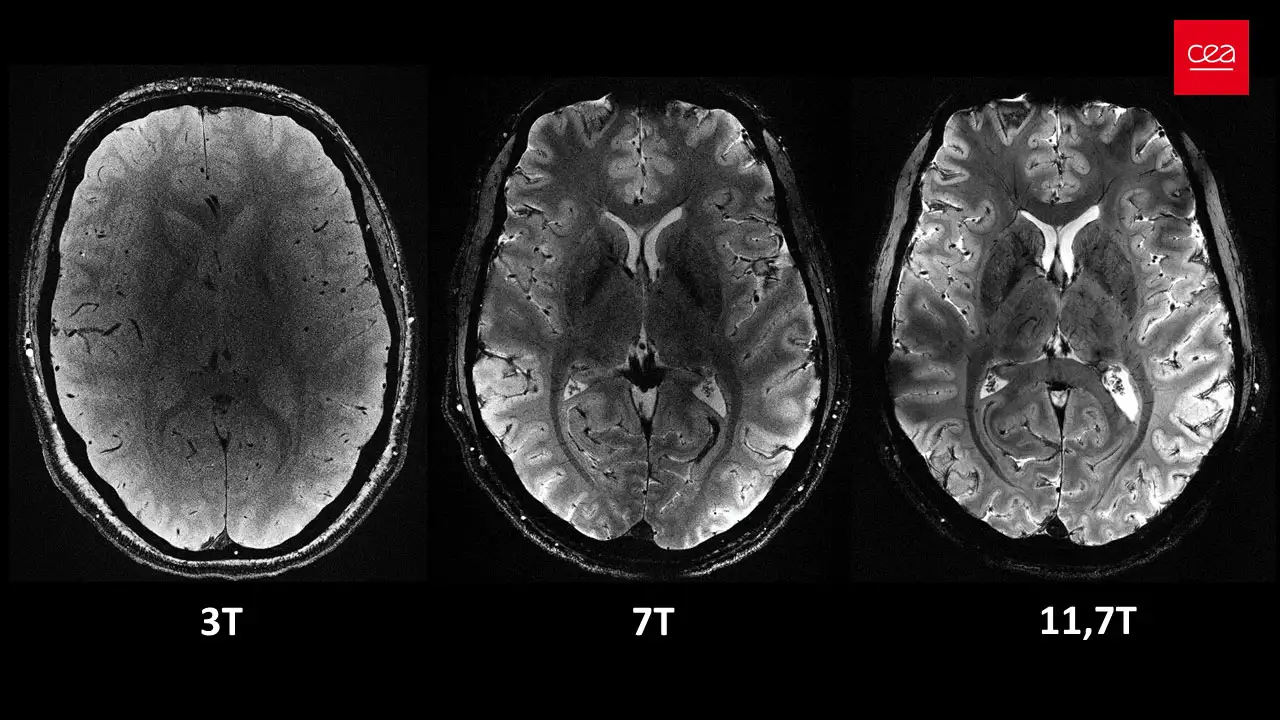

Во Франции создали томограф Iseult мощностью 11,7Т (Тесла) – это самый мощный прибор для проведения МРТ на данный момент. Максимальные возможности устройства предыдущего поколения были ограничены 7Т.

Новый прибор способен за минуты сделать то, с чем менее продвинутые устройства справляются за несколько часов. Результатом становятся изображения высокой точности и четкости. Сама процедура более комфортна для пациента, так как занимает менее длительное время.

Авторы надеются, что новое устройство позволит узнать больше о мельчайших изменениях в головном мозге, возникающих при нейродегенеративных и психиатрических заболеваниях, что улучшит диагностику и сделает терапию более результативной.